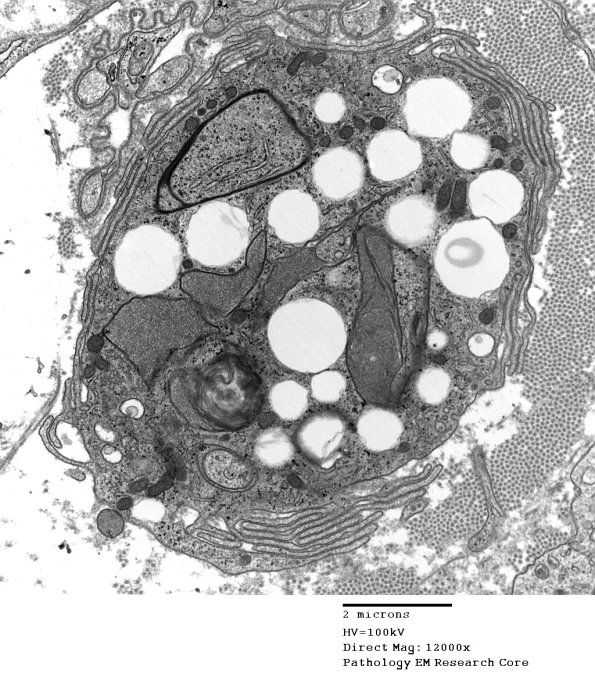

3G2-4 Higher magnification of the second macrophage with numerous pseudopods and partially metabolized Schwann cell, myelin and axonal debris.